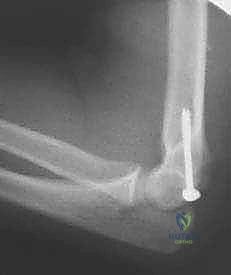

كسر اللقيمة الإنسية بالمرفق: دليل شامل للعلاج الجراحي والتعافي مع الأستاذ الدكتور محمد هطيف

تعرف على كسر اللقيمة الإنسية بالمرفق، أسبابه، أعراضه، وخيارات العلاج الجراحي المتقدمة (ORIF). يقدم الأستاذ الدكتور محمد هطيف في صنعاء خبرة …